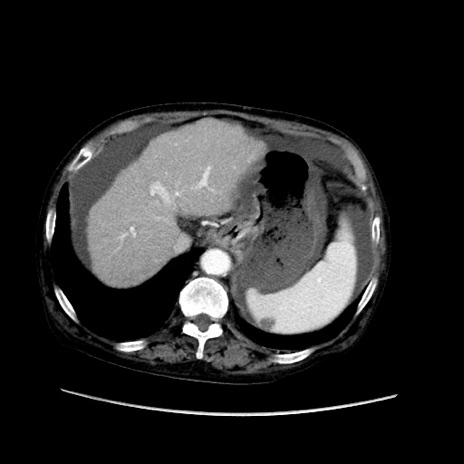

症例31(横断像)

【症例】80歳代 女性

【主訴】腹部膨満感

【現病歴】他院にて肝硬変にてフォロー中。1週間前から便秘、腹部膨満感、臍部腫瘤あり受診となる。

【既往歴】肝硬変

【身体所見】腹部膨隆あり、皮膚変化なし、疼痛なし。

【データ】WBC 4600、CRP 0.25